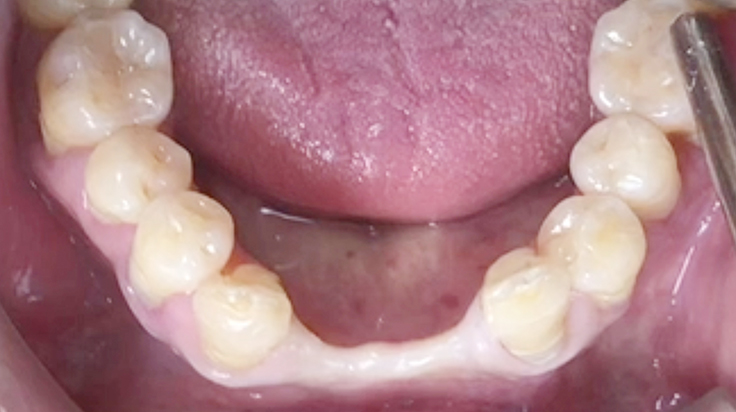

Horizontal ridge augmentation

A surgical procedure to increase the width of alveolar ridge which have been resorbed after tooth or teeth were lost